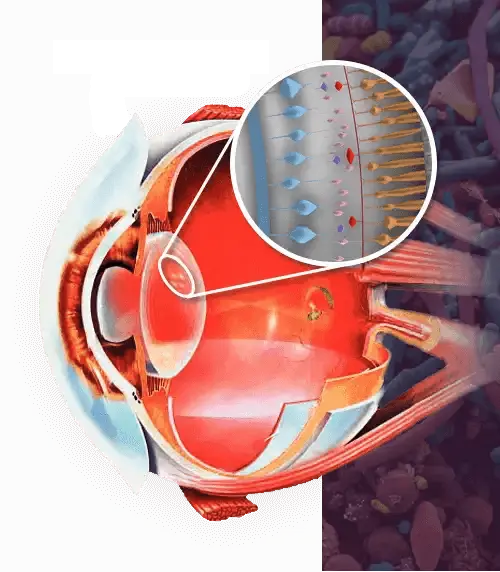

¡La causa principal de una mala visión es el mal funcionamento los músculos de los ojos!!

Los músculos oculares ayudan a enfocar correctamente la imagen en la retina.

Alteraciones musculares pueden afectar el enfoque visual natural del ojo.

Cuando el cristalino se deforma, la nitidez visual puede verse comprometida.

La elasticidad del cristalino es clave para una visión saludable y natural.

Con el tiempo, esta capacidad puede disminuir por diversos factores externos.

Apoya la función muscular ocular

Los componentes de Vizinex ayudan a mantener el tono del músculo ciliar, favoreciendo la estabilidad del cristalino y evitando tensiones excesivas.

Favorece la circulación ocular

Su fórmula contribuye a mejorar la elasticidad de las arterias oftálmicas y estimula un flujo sanguíneo saludable hacia la retina y la córnea.